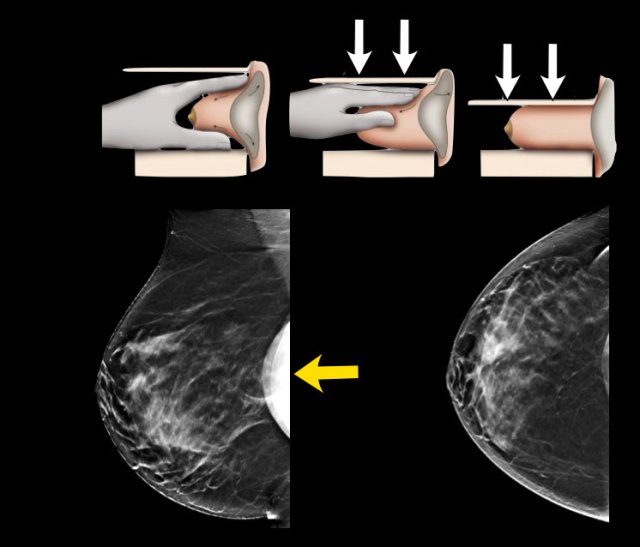

Eklund technique

Special views can be performed such as the Eklund views.

By pushing the implant posteriorly and pulling the breast tissue anteriorly better visualization of the fibroglandular tissue can be achieved.